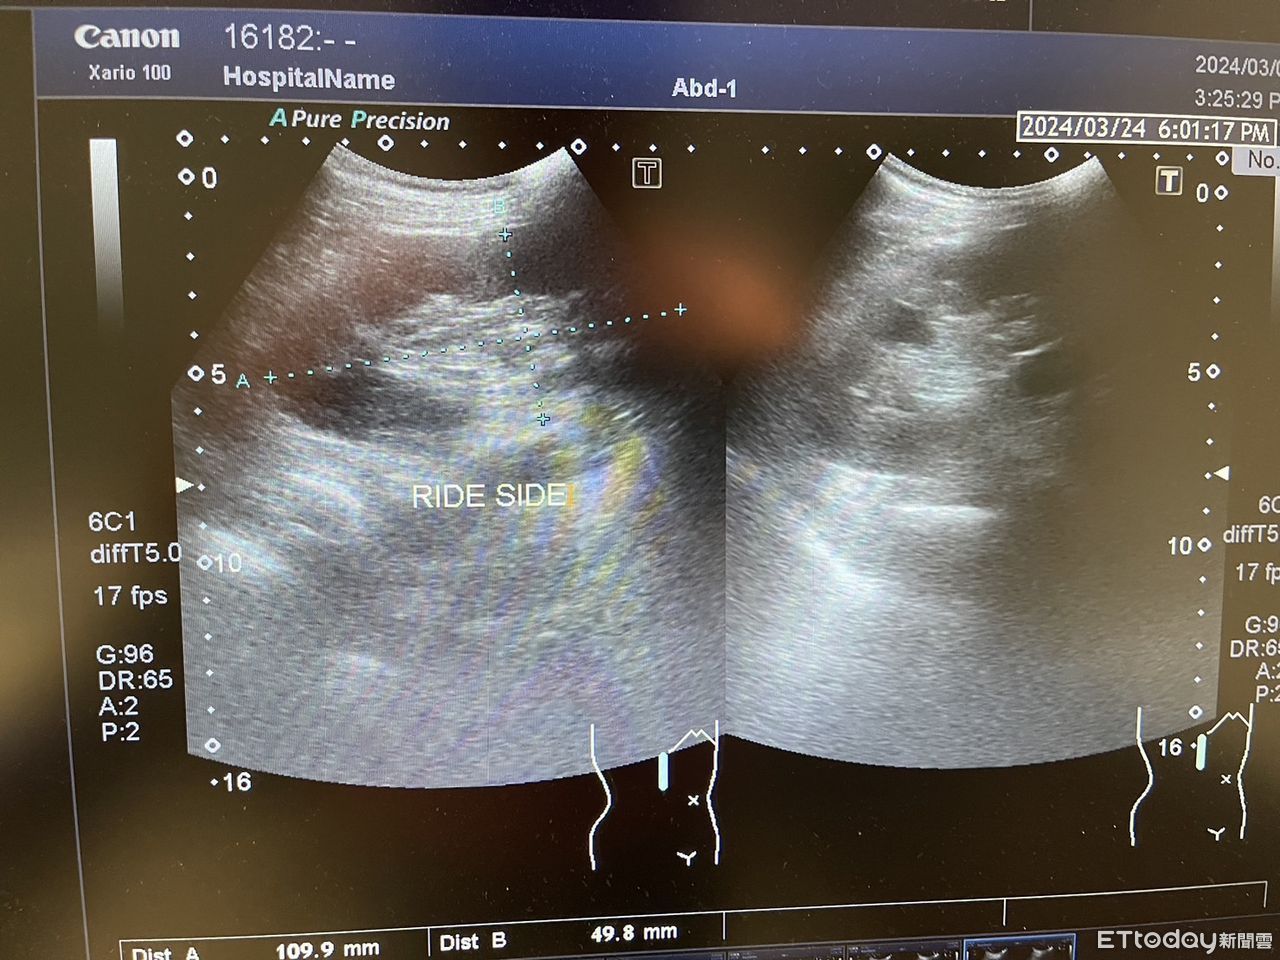

▲右邊腎臟上面應該要有肝臟,但是超音波顯示卻沒有。(圖/記者吳奕靖翻攝)

一名70歲的男子因為腰痠背痛來到張美玉醫師的門診,張美玉醫師進行超音波掃描左邊腎臟時,赫然發現脾臟大到像是肝臟,當場就覺得奇怪,結果掃右邊腎臟時,卻沒有找到肝臟?正當張美玉醫師一頭霧水時,她才驚覺自己看到了「難得一見」的「內臟逆位」。